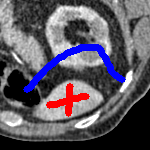

We now introduce two recent methods that incorporate user input to perform selective segmentation. Each involves input in the form of foreground/background regions to indicate relevant structures of interest. An example of this can be seen in Fig. 18, where red regions indicate foreground and blue regions indicate background. We compare against the work of Nguyen et al. Nguyen:12 , which uses a similar convex relaxation framework to the proposed approach, and Dong et al. SRW , which uses a variation of the random walk approach. We summarise the essential aspects of each approach in the following.

Test Images. We will perform initial tests on the images shown in Figs. 5–7. We have provided the ground truth and initialisation used for each image. Test Images 1–3 are synthetic, Test Image 4 is an MRI scan of a knee, Test Images 5–6 are abdominal CT scans, and Test Images 7–9 are lung CT scans. They have been selected to present challenges relevant to the discussion in §2. We focus on medical images as this is the application of most interest to our work. In the following we will discuss the results in terms of synthetic images (1–3) and real images (4–9). We also test the proposed approach on a larger data set of 30 CT images (a sample of which is presented in Fig. 18), comparing against existing selective methods detailed in §3.

In order to further establish the robustness of our method, we now introduce the results of testing our approach against competing interactive segmentation methods on a larger data set. The results are presented in Fig. 17, showing a boxplot of accuracy in terms of TC on a set of 30 CT images (excluding outliers). The target structure we consider is the spleen, as this consists of a relatively homogeneous foreground, appropriate for the approach considered. The data has been manually contoured providing ground truth data for the image set. We compare CAC Nguyen:12 and SRW SRW against our method with five variations of user input for each image. It is worth emphasising here that the input used in the tests is identical for each approach and was not refined in any way. It was designed to mimic what a user, unfamiliar with each approach, might select intuitively. A representative example for three images is shown in Fig. 18. This shows foreground (red) and background (blue) user input regions. For our method, we define the red region as as discussed in §1 and enforce hard constraints on the blue region. We refer to the results of the proposed approach using this input as Ours (i). We also include results of randomising the user input in an identical way to §7.3. For each image we generate 1000 simulated user input choices, which we present as Ours (ii). It is important to note that the difference between Ours (i) and (ii) is only the definition of . The method and parameters are fixed between each.